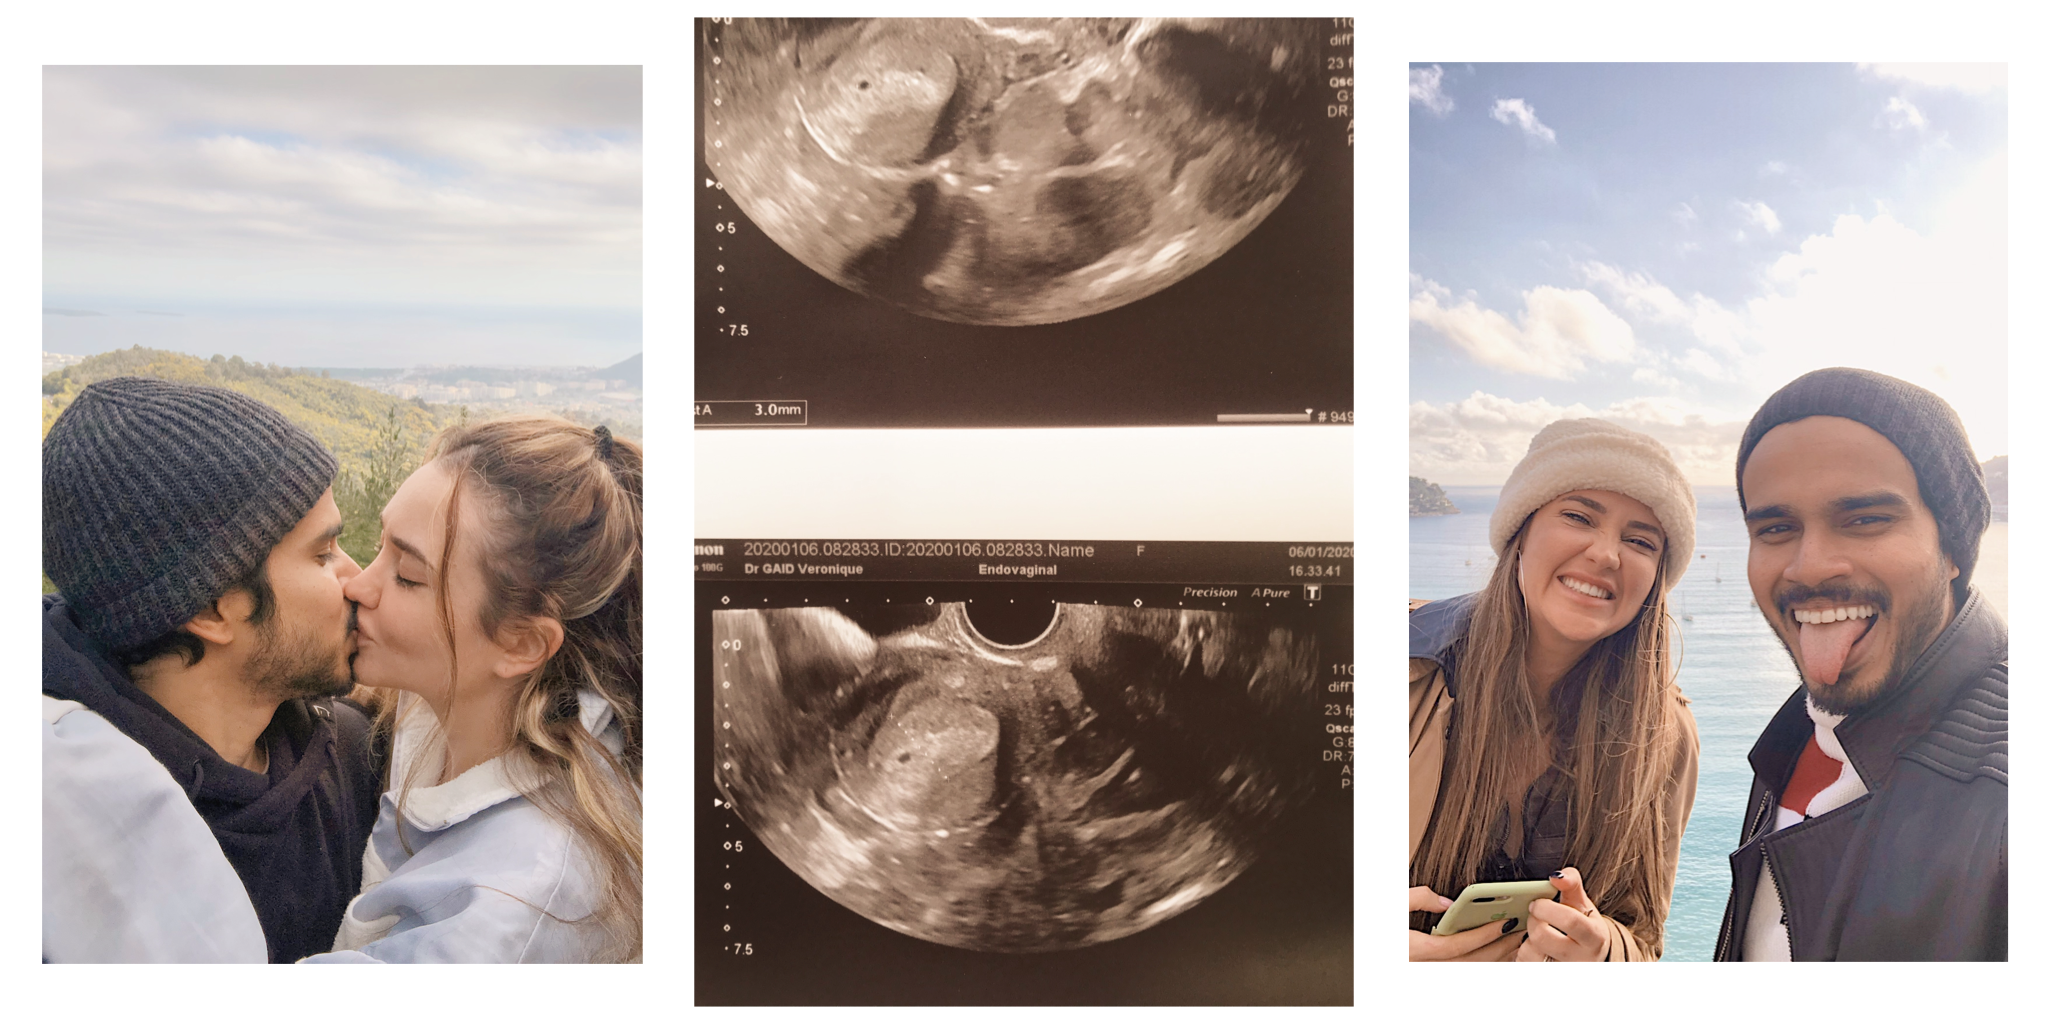

As she started the ultrasound she asked me again in a more serious tone when my nipples pain started, and I noticed that something was happening, so I looked at the screen on my right, and saw this very tiny dot, which I instantly thought was a new endometriosis cyst. I asked her if everything was fine, and she told me that I’ll need to pee on a stick and come back with it.

I just wanted to scream and jump into my husband’s arms, kiss him and tell him that he was going to be a dad in just 9 little months. My emotions were all so strong and all over the place, and I wanted to let them out, but I tried to remain as calm as I could while I was in the doctor’s office, looking at my husband with a lot of pride, love, and excitement while the doctor was filling the prescription she was about to hand to me a few minutes later, with the name of different pregnancy vitamins, and some pregnancy routine blood work, as well as the picture of our tiny little 5 weeks old naturally implanted embryo.

The picture from the ultrasound that was supposed to go to our IVF file had become the very first picture of our son.

1. One of our casual hike with the dogs in the South of France, 2. Our very first ultrasound image of our little boy, 3. Our first French date before Christmas 2019.